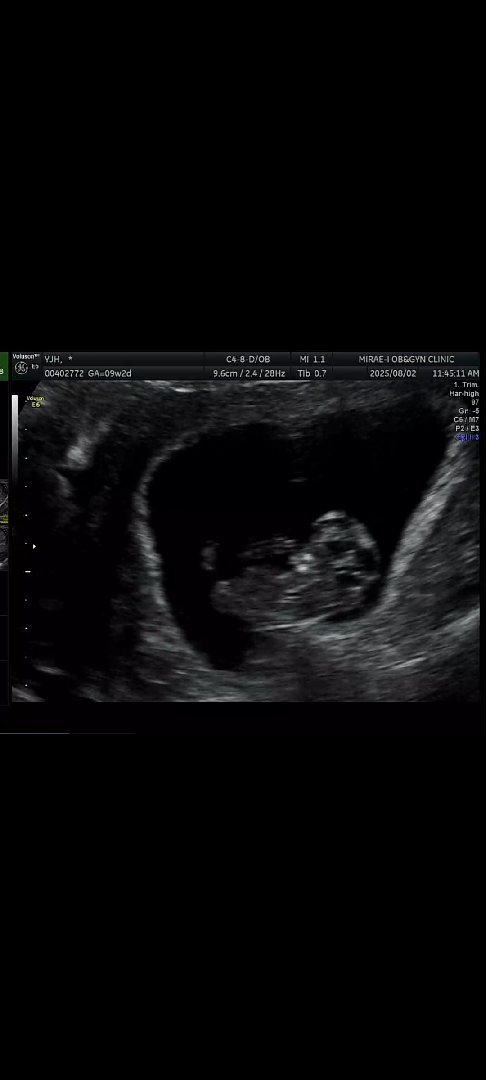

12주 2일차~~각도법으로 아들.딸 구분 부탁 드려요:)

저는 초보라 아무것도 보이지 않네요ㅠ 잘 아시는 분들 부탁 드려요ㅠㅠ

사진이 너무 흐릿해서 안보이네용 ㅠㅠ